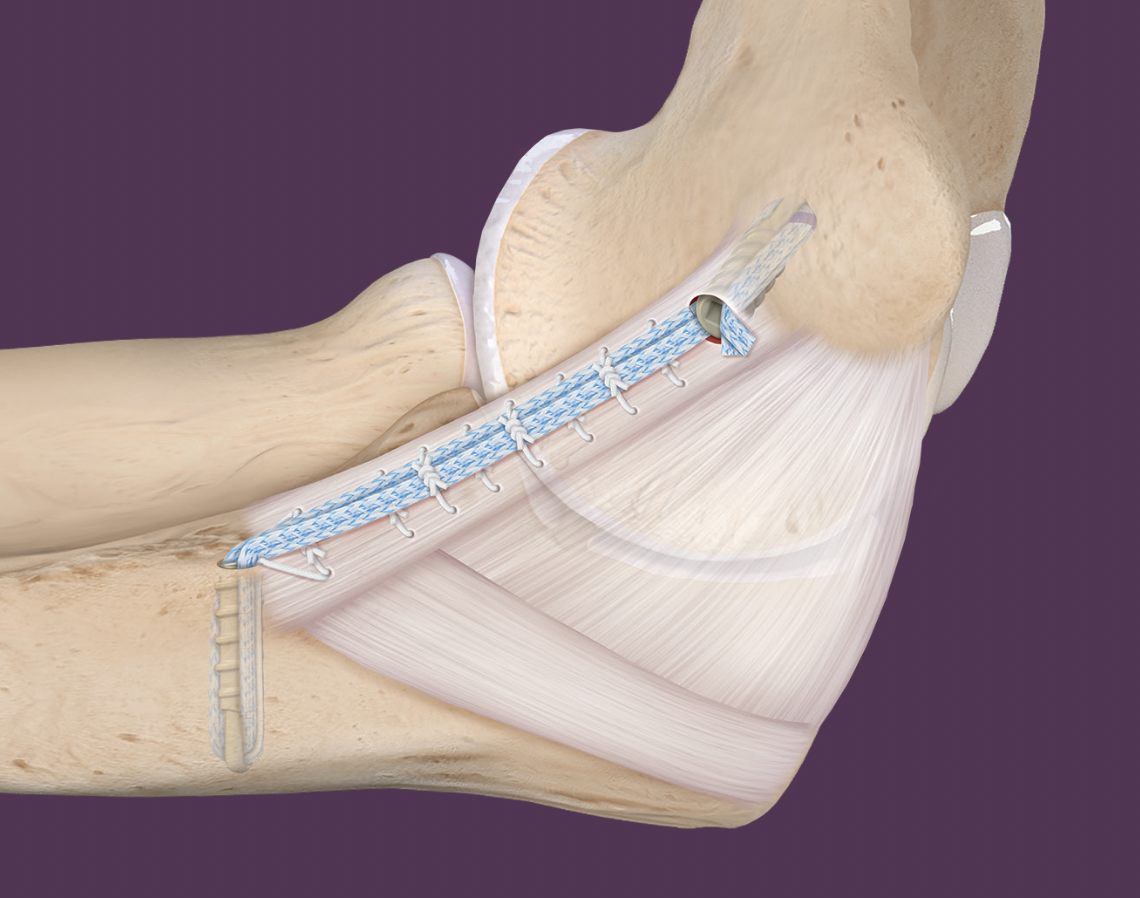

Primary UCL repair with internal brace augmentation

Technique

Arthrex internal brace UCL surgical technique PDF

Vumedi primary UCL repair with internal brace augmentation video

Arthroscopy techniques UCL repair with internal brace augmentation PDF

Arthrex UCL repair and internal brace video

Medial incision over medial epicondyle

- protect ulna nerve

- split FCU

- expose ulna collateral ligament

- repair avulsion from medial epicondyle / sublime tubercle as indicated with anchor

- ensure isometric

Results

Repair with internal brace versus reconstruction

- 461 athletes with repair + internal brace versus reconstruction

- repair if avulsed from medial epicondyle or sublime tubercle

- UCL repair: revision rate 9%, return to sport 99% at mean 9 months

- UCL reconstruction: revision rate 8%, return to sport 98% at mean 13 months

- no difference in outcomes but earlier return to sport with repair